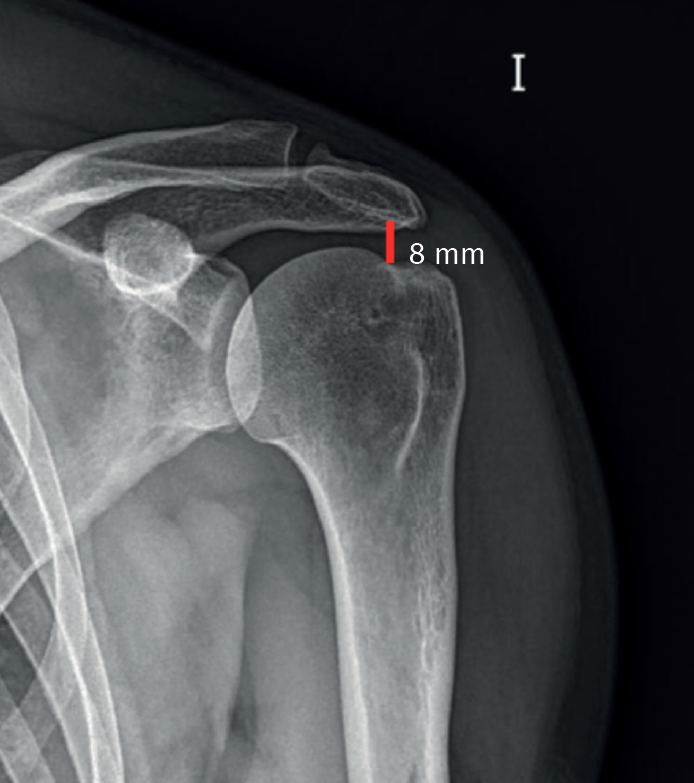

Another indicator of irreparability is the acromiohumeral distance (AHD). This is measured according to the classification proposed by Hamada et al. in 1990(24) (and modified in 2011)(25) for MRRC based on an anteroposterior plain radiograph of the shoulder, comprising 5 grades: in grade 1, AHD measures 6 mm or more (Figure 4); in grade 2 it narrows and measures 5 mm or less; in grade 3 acetabularization of the acromion is observed secondary to ascent of the humeral head; grade 4 is subdivided into grade 4A with narrowing of the glenohumeral joint space without acetabularization of the acromion and grade 4B with acetabularization; and lastly grade 5 consists of humeral head collapse. An AHD of less than 6 mm is considered to be an independent predictor or irreparability. Thus, those cases of MRRC corresponding to Hamada grade 2 or higher are considered to be irreparable.